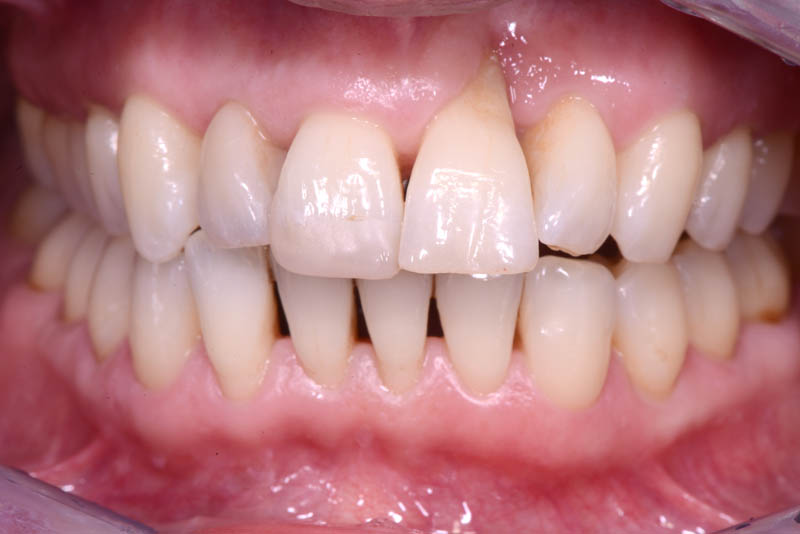

Following an initial phase of non-surgical periodontal therapy aimed at removing subgingival calculus, Dr. Anna Mariniello performed both upper and lower alignment using a lingual, non-bracket orthodontic technique, employing active retainers applied to the lingual surfaces of the teeth.

At the end of the orthodontic treatment, a coronally advanced flap was performed according to the De Sanctis and Zucchelli technique, involving papilla preservation and connective tissue grafting, to restore the gingival contour and the papilla between teeth 21 and 22.